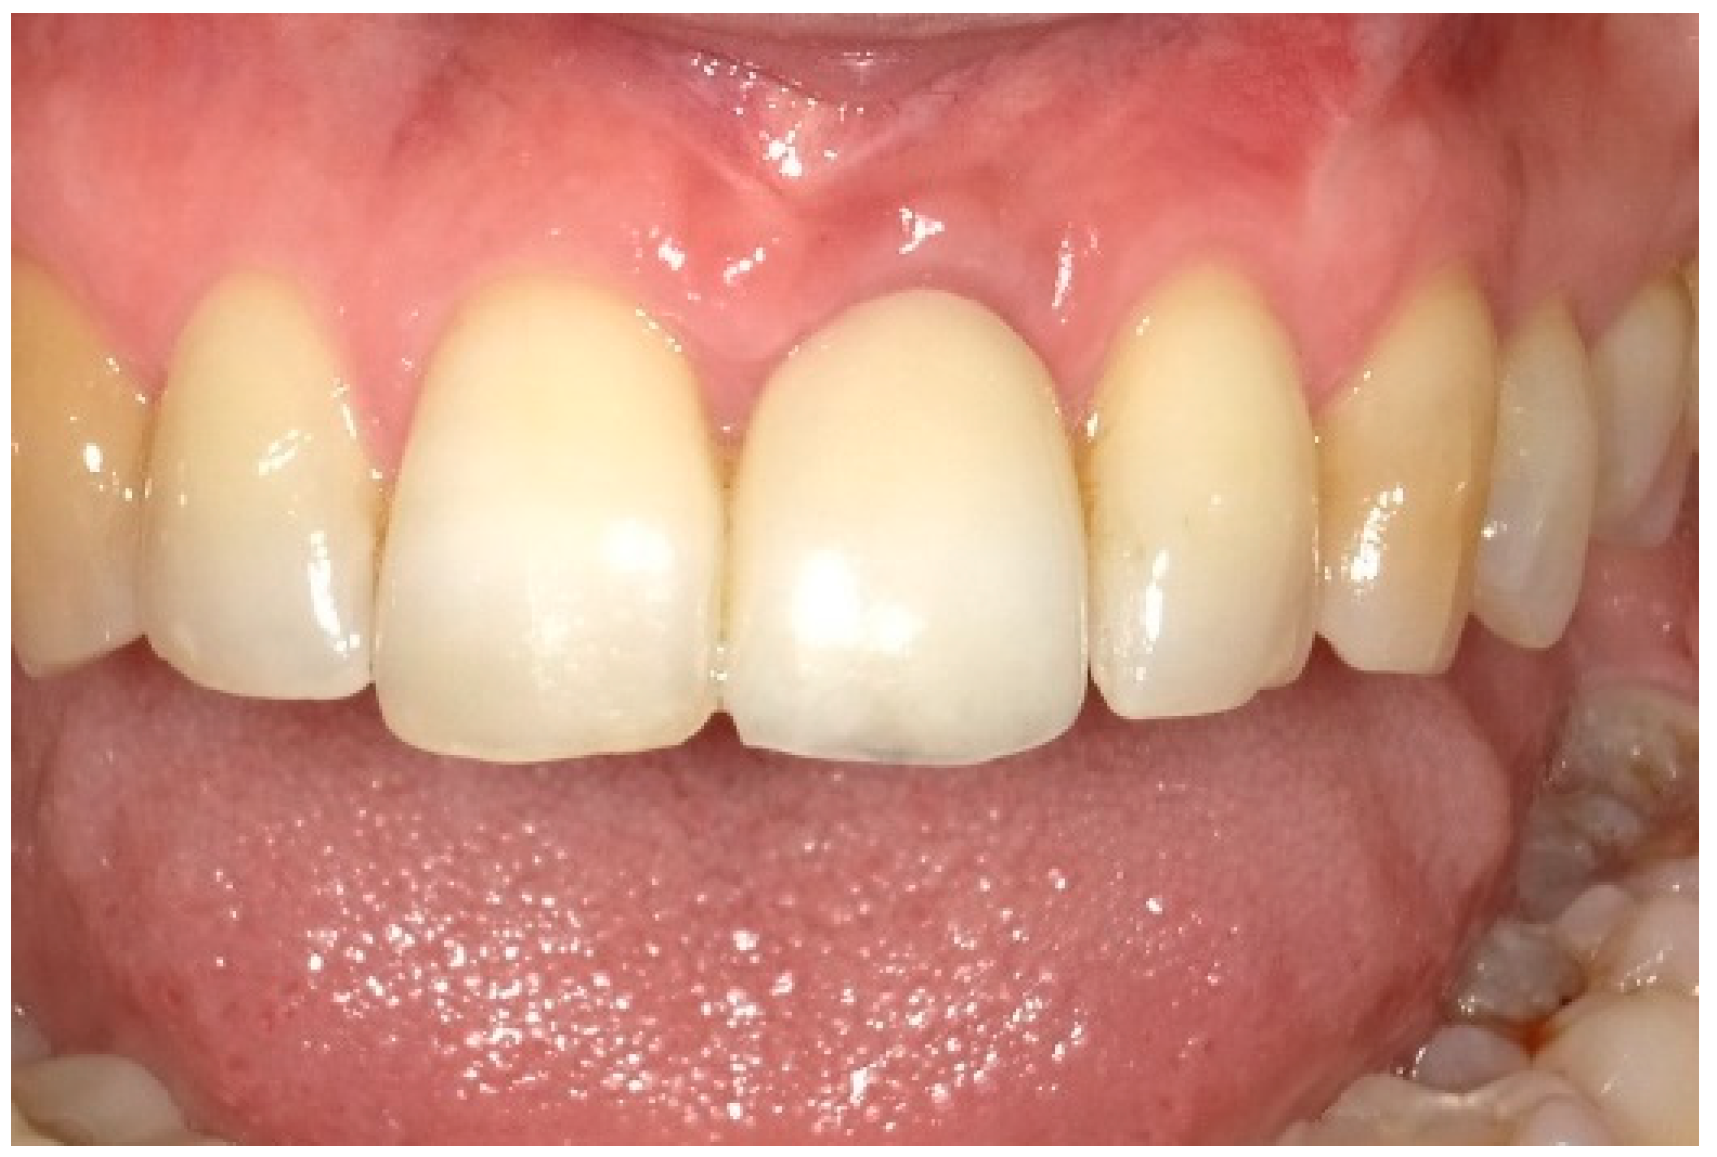

7. Outcomes

| Midfacial mucosa level at Tpre (mm) | 3.0 | 2.0 | 5.0 |

| Midfacial mucosa level at T9 (mm) | 5.0 | 6.0 | 6.0 |

| Midfacial mucosa level at T12 (mm) | 5.0 | 6.0 | 6.0 |

| Mesial papilla | 1 | 1 | 0 | 0 | 2 | 2 |

| Distal papilla | 1 | 1 | 0 | 0 | 2 | 1 |

| Curvature of the facial mucosa | 1 | 1 | 2 | 2 | 1 | 2 |

| Level of the facial mucosa | 0 | 2 | 2 | 1 | 1 | 2 |

| Root convexity/soft tissue color and texture | 0 | 1 | 2 | 2 | 0 | 1 |

| Total | 3 | 6 | 6 | 5 | 6 | 8 |